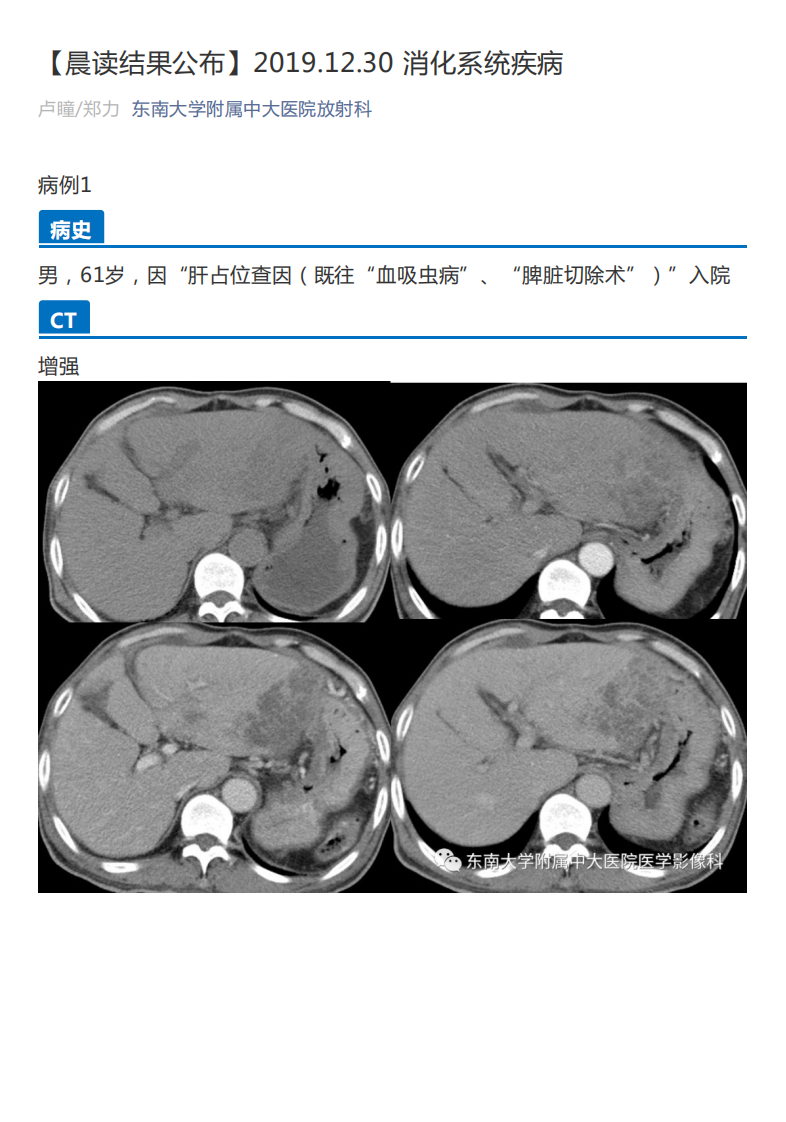

中大放射

20191230_2【晨读结果公布】2019.12.30消化系统疾病.pdf